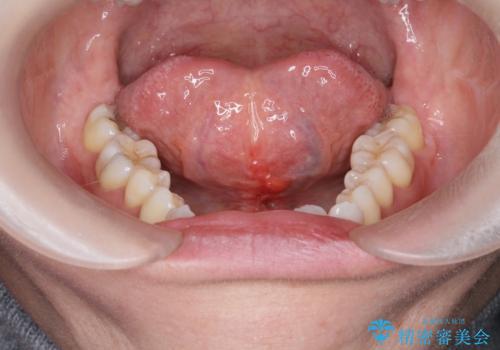

滑舌を改善したい 舌小帯の形成術

- 長年気になっていた、滑舌の問題を改善すべく舌小帯の形成手術を希望され来院されました。

舌の小帯が長く、舌の動きを制限しているため手術により改善を計画します。

手術は5分程度で終わり、術後の大きな痛みも訴えられる方はほとんどいません。